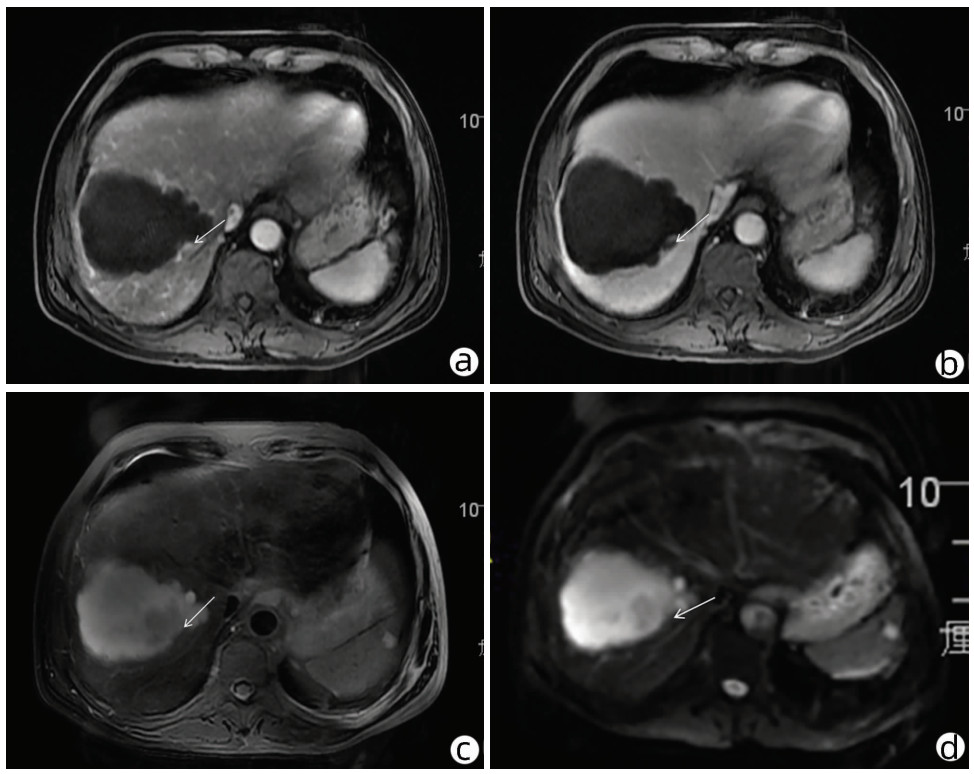

A case of eosinophilia mainly manifesting as liver injury

Hao WU, Xin ZHENG, Lei ZHU, Dong YANG

2022, 38(4): 883-885. DOI: 10.3969/j.issn.1001-5256.2022.04.027

Abstract(2133) HTML (304) PDF (2636KB)(146)

Abstract: